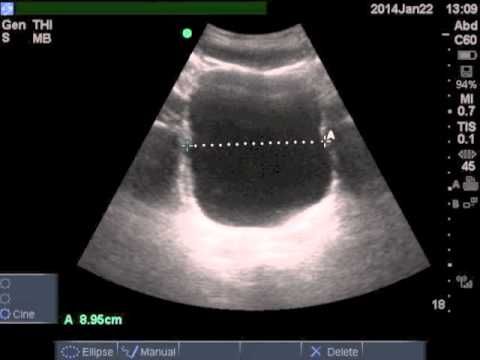

Також визначення ВОМ проводять за допомогою УЗД. Його проводять двічі. Перший раз з повним міхуром, а потім за 5-10 хвилин після сечовипускання. Визначають кількість рідини за спеціальною формулою. До уваги беруться висота, ширина і довжина міхура. Для того, щоб результат ВОМ був точним, процедуру проводять 3 рази.

Щоб провести визначення залишкового об’єму сечі (ВОМ) проводять ультразвукове дослідження в 2 етапи. Для початку проводять діагностику при повному сечовому міхурі. Потім просять хворого спорожнити мочевик і посидіти на протязі 15 хвилин, а потім знову розглядають на моніторі апарата змінений орган. Різниця в розмірах і обсяг видима по УЗД, прораховується за нормативними таблицями.

Великий обсяг залишкової сечі може визначатися при промацуванні контурів сечового міхура. Більш точно її кількість можна побачити при проведенні УЗД після сечовипускання.